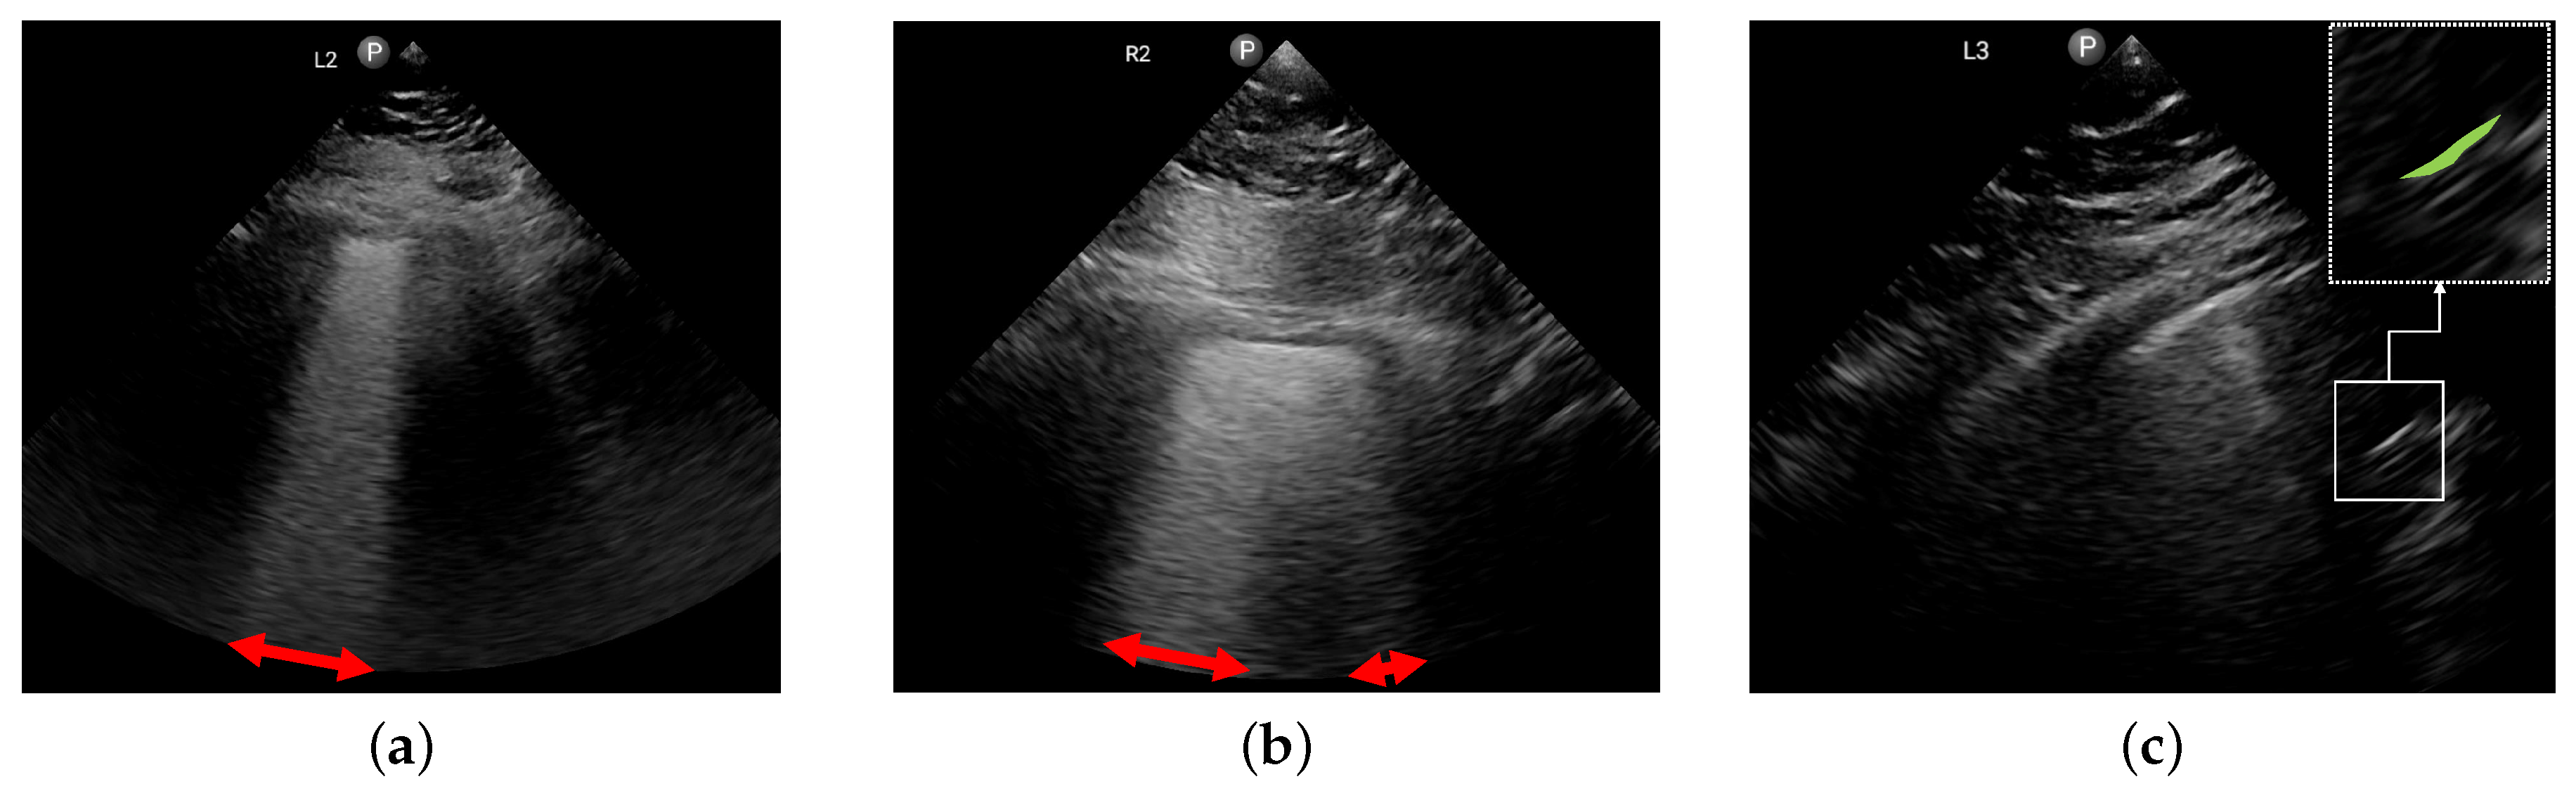

2.2. Approach